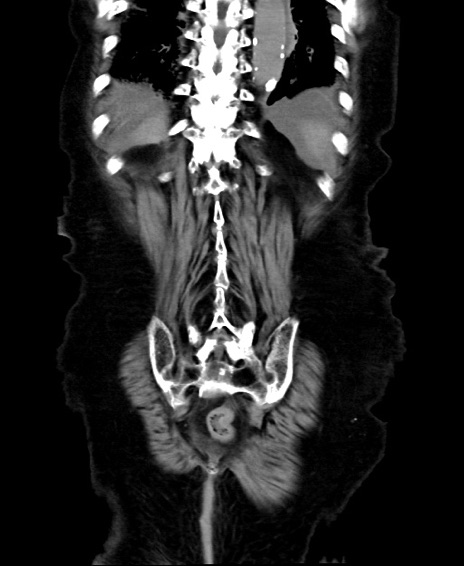

矢状断像